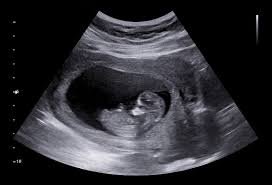

Obstetric Ultrasound

Essential for monitoring fetal development during pregnancy. We perform NT scans, anomaly scans, and growth scans with utmost care and clarity.

Our advanced imaging techniques ensure detailed visualization of the fetus, helping in early detection of potential issues and ensuring maternal and fetal well-being.